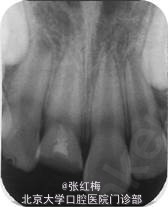

X线示:11、21发育9期,根管粗大,未见明显根折线,根尖周未见病变影,骨硬板清晰,未见牙槽突骨折线;

检查:11粘接断冠完好,叩(-),不松,龈未见异常,冷测有感觉,无疼痛;X线:11根 尖继续

形成中,根周膜清晰

治疗后八个月复查